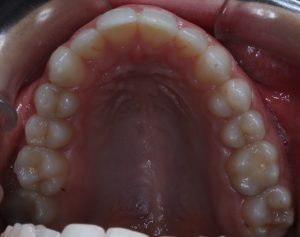

Maloclusión

Se caracteriza por una alineación incorrecta de los dientes, donde los dientes superiores e inferiores están en una relación normal, pero hay una falta de espacio que provoca que los dientes se solapen o estén apiñados.

Este problema puede generar dificultad para mantener una correcta higiene dental y afectar la estética de la sonrisa